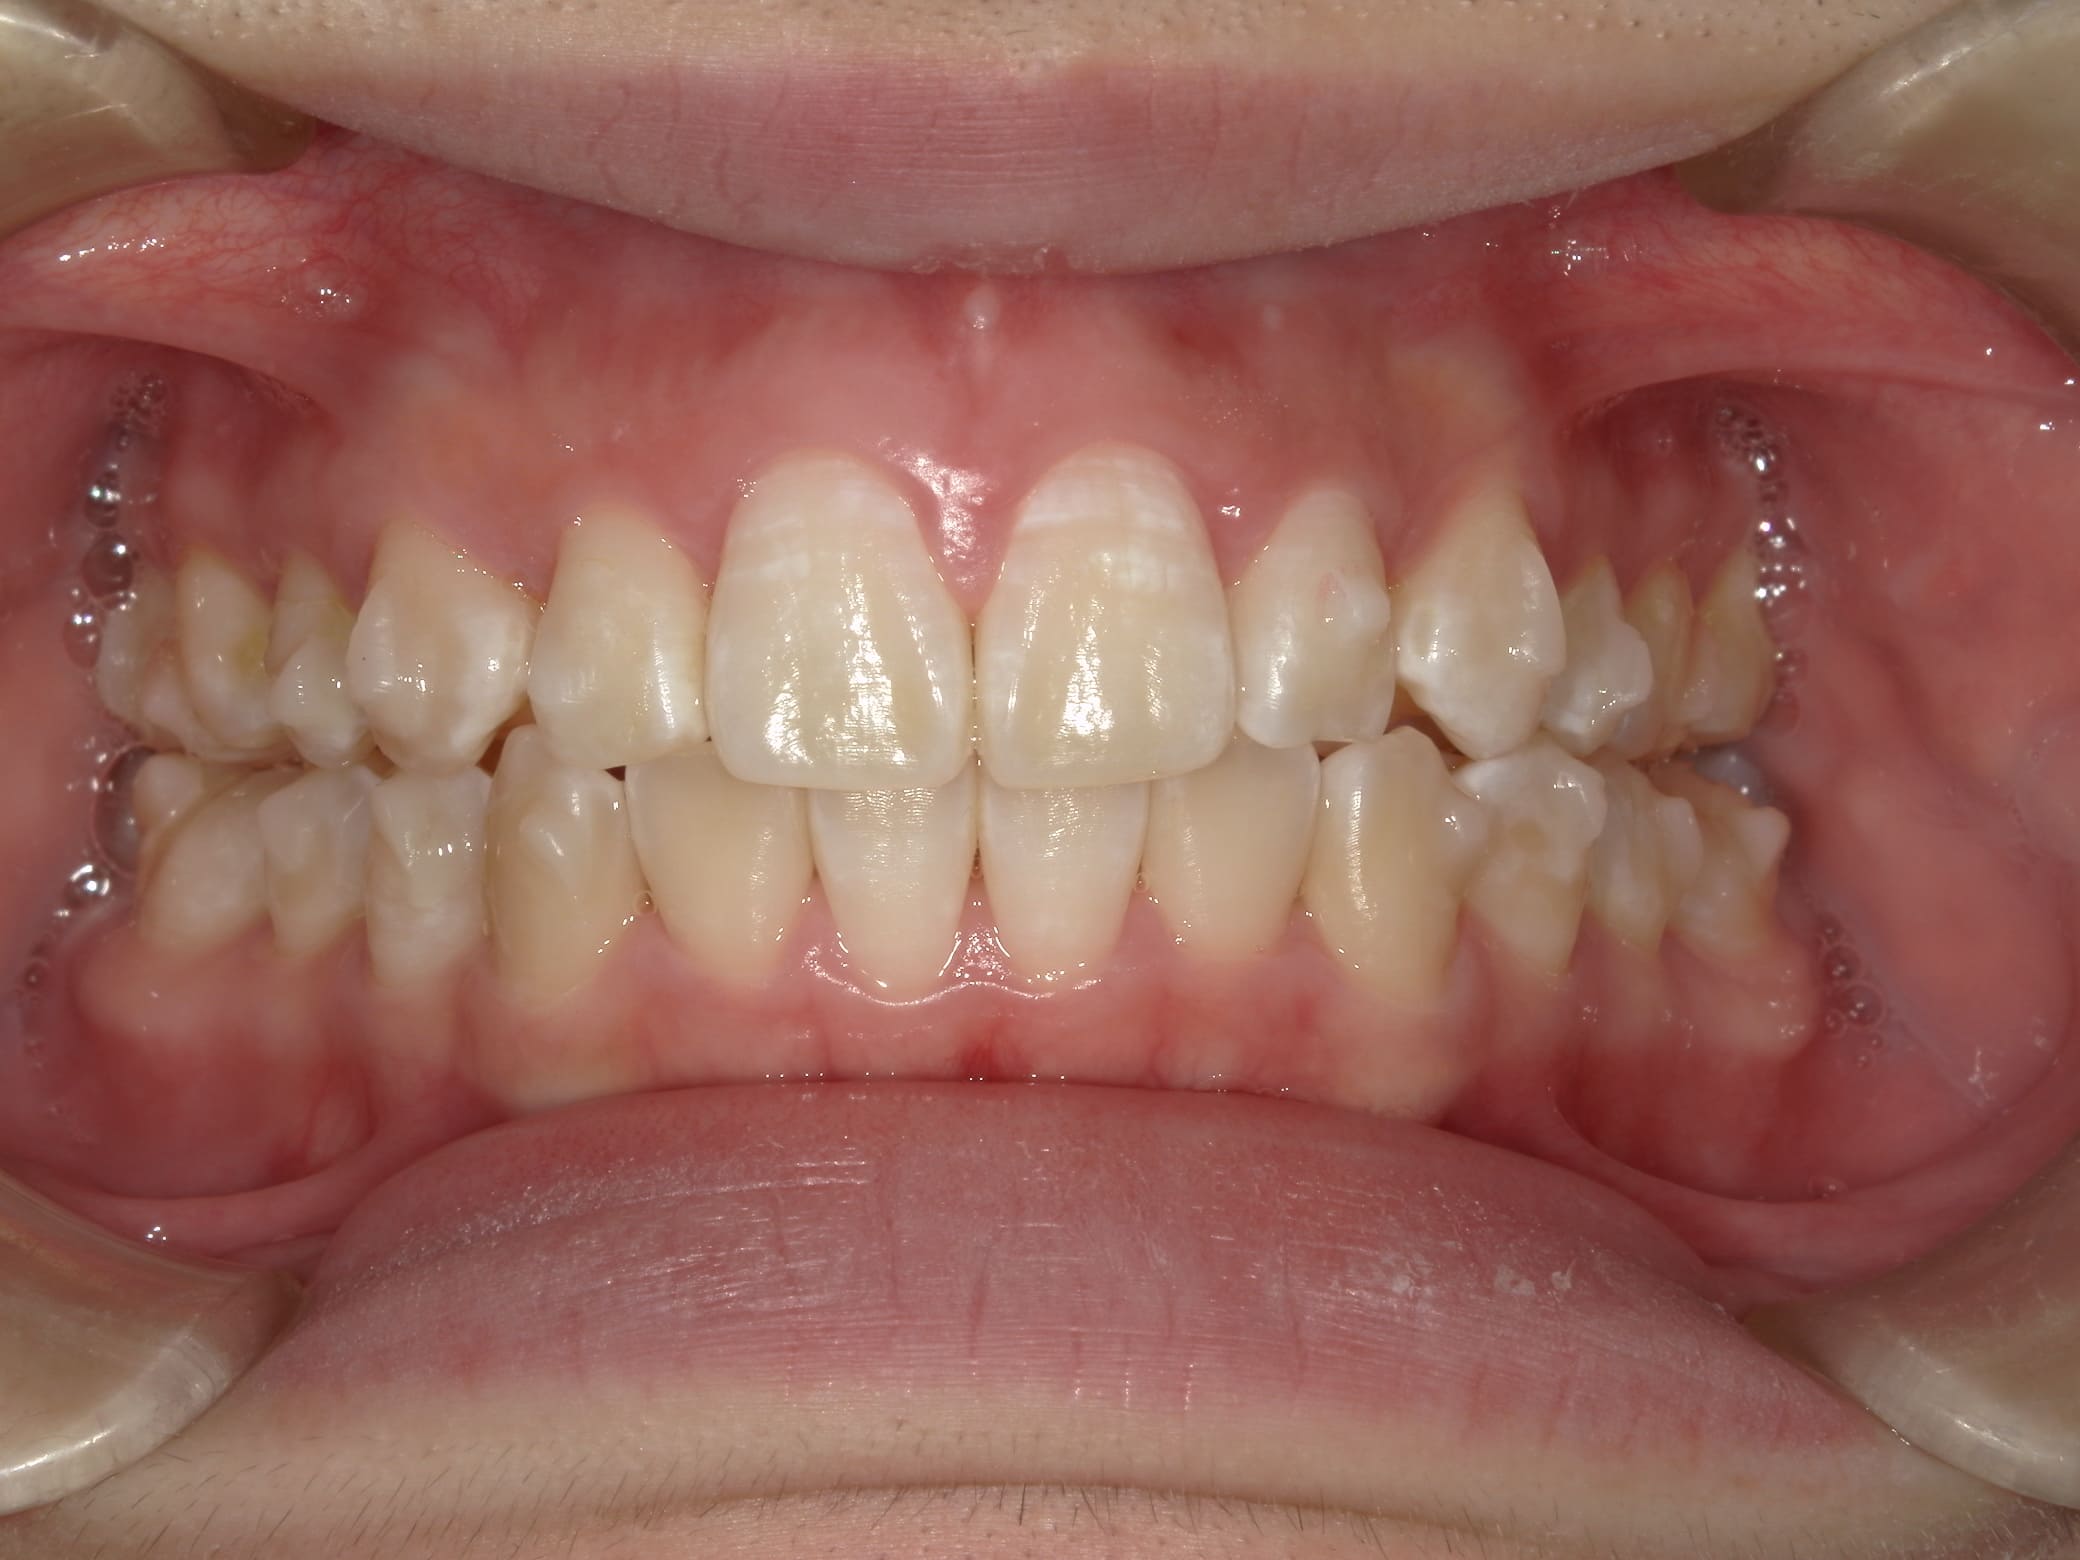

| 年齢・性別 | 21歳 |

|---|---|

| 主訴 | 叢生が気になる・前歯に埋伏歯がある |

| 治療期間・回数 | 6ヶ月 |

| 費用 | 935,000円 |

| 上顎の左側3番が埋伏していたため、上顎左右の3番および親知らずを抜歯し、矯正治療を行いました。 治療開始からおよそ6ヶ月で歯列が整い、審美的にも機能的にも良好な結果が得られた症例です。 |